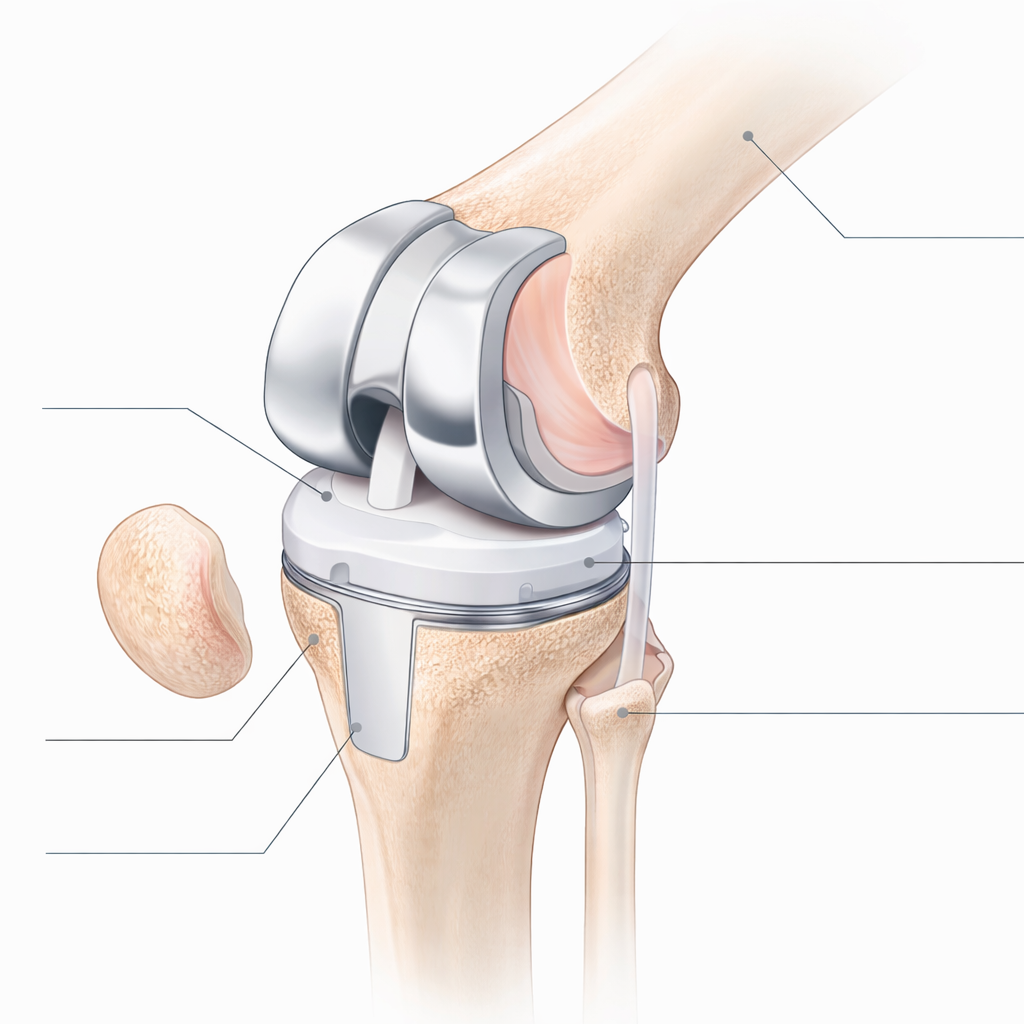

Patología quirúrgica (Publicaciones/Libros): "Ilustración médica isométrica de una articulación de rodilla humana mostrando una prótesis total. Estilo 'medical textbook' contemporáneo, colores pastel limpios, etiquetas de líneas finas (sin texto), iluminación global suave. Fondo sólido para fácil recorte. Precisión anatómica profesional."